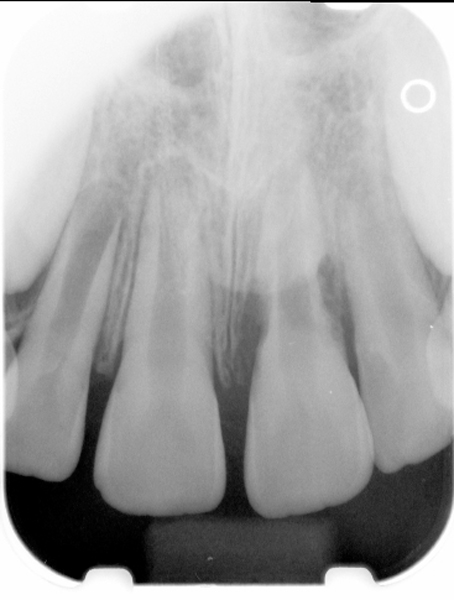

Fig 1. Preoperative radiograph showing apical bone loss.

Figure 1

Clinical procedure: If apical bone loss is present (Figure 1) a collagen/gelatin sponge (eg, Gelfoam®, Pfizer Inc., www.pfizer.com) can be placed apically so that the MTA can be delivered to the desired working length. (Any other surgical resorbable sponge would also work, such as OraPlug® [Salvin Dental Specialties, www.salvin.com], Surgifoam® [Midwest Dental, www.mwdental.com], or Surgispon® [Aegis Lifesciences, www.surgispon.com]). This is done by taking a small piece (2 mm x 2 mm) of the resorbable sponge and pushing it down to and through the root apex with an endodontic file. Once this is done, MTA is packed down the canal with a custom-fitted cone. The clinician can use a rubber stopper on the gutta-percha cone to know the exact length of MTA placed in the apical third (Figure 2). Once the apical third is sealed with 3 mm to 5 mm of MTA, the remaining coronal canal space can be back-filled using a warm gutta-percha technique (Figure 3).